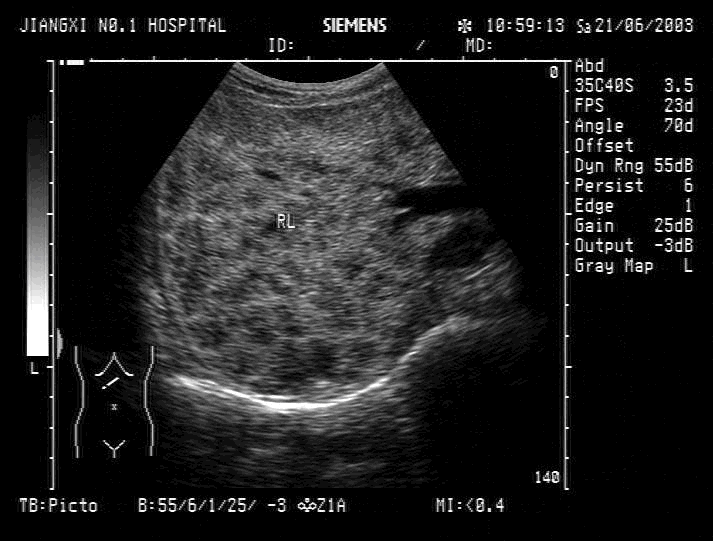

男,60岁,胆囊结石病史多年,脾大小正常,有疫区接触史。结合超声检查如图,诊断为 CF20160315_52.gif

• A.肝血管瘤

• B.血吸虫肝

• C.肝癌

• D.肝硬化

• E.脂肪肝